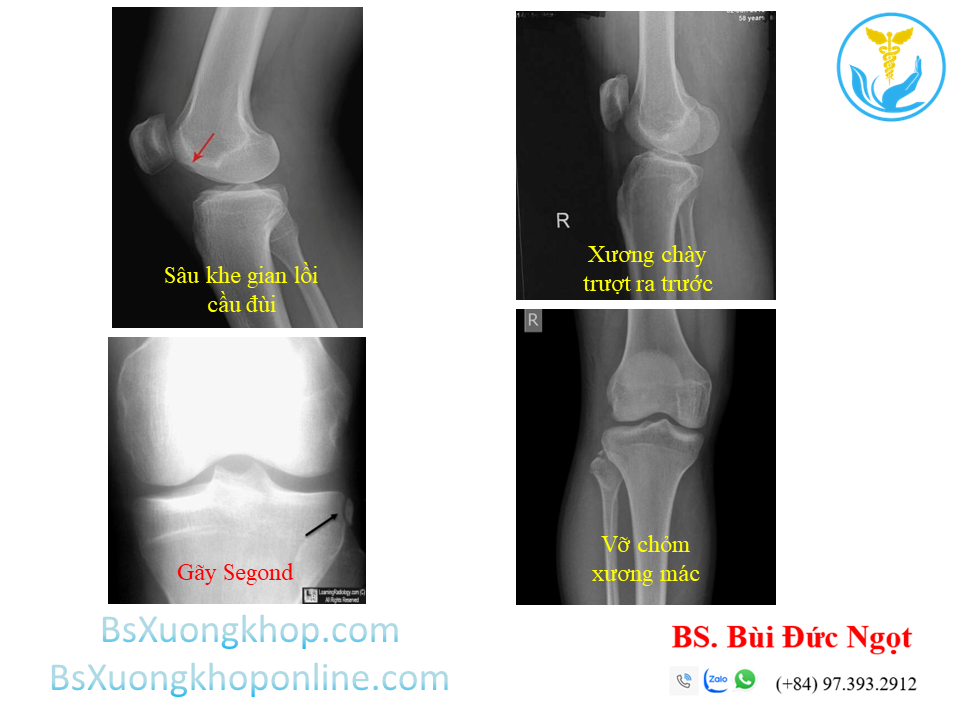

2.1. Chụp XQ khớp gối thẳng - nghiêng

Dây chằng chéo không cản quang, do đó không thể nhìn thấy tổn thương trực tiếp trên phim Xquang khớp gối.

Các dấu hiệu gián tiếp có thể gặp trên phim:

- Khe gian lồi cầu đùi sâu.

- Xương chày trượt ra trước.

- Gãy Segond (Segond’s fracture) hoặc vỡ chỏm xương mác (arcuate’s fracture).

- Tràn dịch khớp gối.